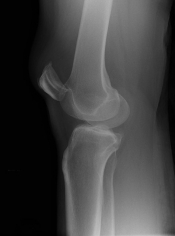

Pijn knie na aanrijding. Wat is de diagnose? Gepost op 15 juli 201715 juli 2017 door netwerkvsseh What’s the Diagnosis? @ emdaily.cooperhealth.org Dit delen: Delen op X (Opent in een nieuw venster) X Share op Facebook (Opent in een nieuw venster) Facebook Delen op LinkedIn (Opent in een nieuw venster) LinkedIn E-mail een link naar een vriend (Opent in een nieuw venster) E-mail Afdrukken (Opent in een nieuw venster) Print Vind-ik-leuk Aan het laden... Gerelateerd